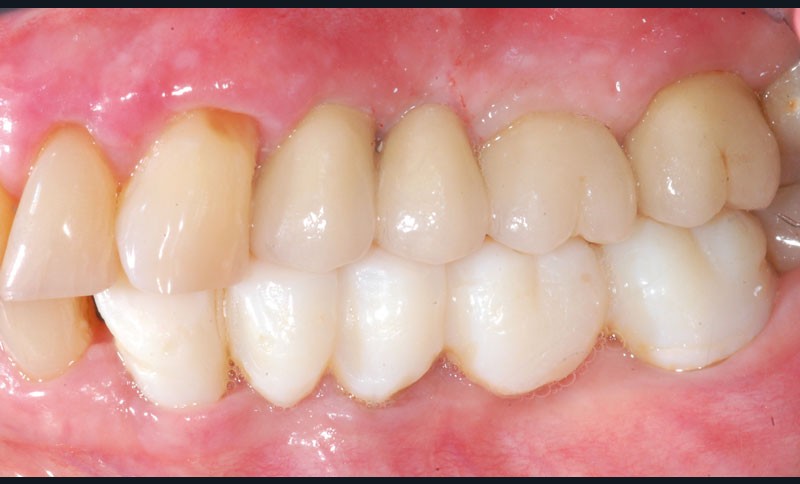

Le bridge 24-26 céramométallique et la couronne unitaire sur 27 sont réalisés. Les piliers CFAO sont transvissés sur les implants, puis les éléments céramo-métalliques sont posés. Le résultat montre un parfait respect du projet prothétique en fonction de la courbe occlusale obtenue avec le bridge transitoire réalisé avec le ProtempTM 4 et une adaptation parfaite.